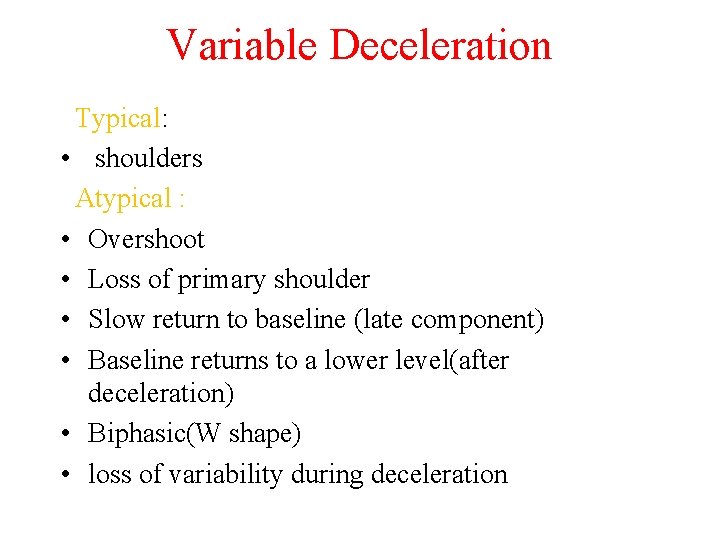

Variable Deceleration Typical: • shoulders Atypical : • Overshoot • Loss of primary shoulder • Slow return to baseline (late component) • Baseline returns to a lower level(after deceleration) • Biphasic(W shape) • loss of variability during deceleration